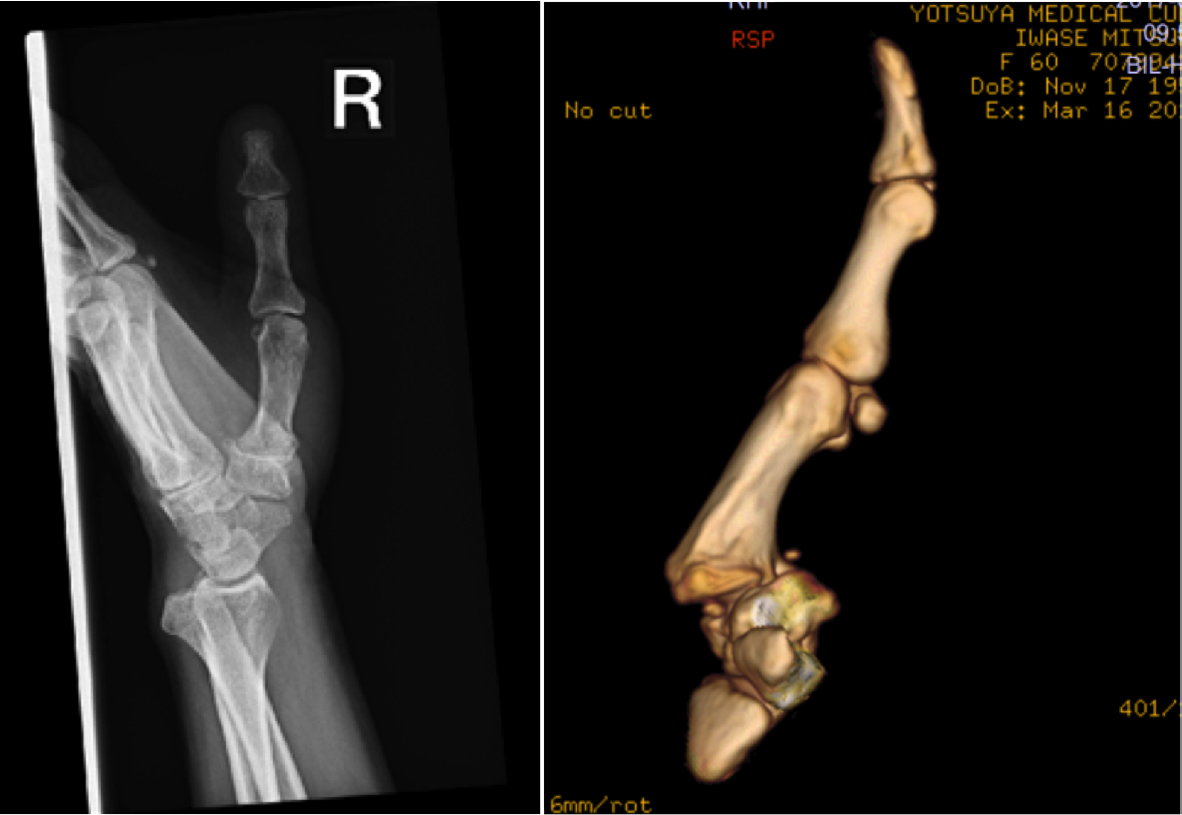

母指CM関節は馬の鞍のような形の関節で、多方向に可動性を持ちます。このため、不安定性がおきやすいとされており、関節周囲の靭帯がゆるみやすく、変形性関節症へ進行すると考えられています。症状が進行すると亜脱臼が進んだり、CM関節の関節軟骨が摩耗したりして変形を生じます。(図1)

(図1)CM関節亜脱臼